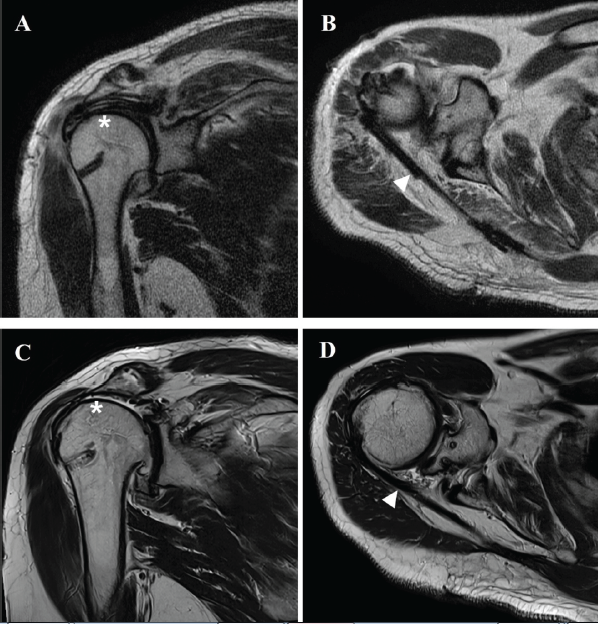

Finally, the interpositional graft was sutured to the LT tendon using the Krackow technique. Postoperatively, the operated arm was immobilized in a 30° abduction shoulder brace for 6 weeks to protect both the reconstructed superior capsule and the transferred tendon. Passive ROM exercises were initiated after brace removal, focusing initially on FE and ER within pain-free limits. When full passive ROM was achieved—typically 8–10 weeks after surgery—active-assisted and active ROM exercises were progressively introduced under physiotherapist supervision. Strengthening exercises were started around 12–14 weeks postoperatively, emphasizing gradual scapulothoracic coordination and controlled eccentric loading. Heavy lifting, resistance training, and overhead activities were restricted for at least 6 months to prevent excessive tension on the graft and allow maturation of the tendon–graft–bone interface. Return to light daily activities was generally permitted at 3 months, and full return to functional activity at 6–8 months postoperatively, depending on patient tolerance and recovery progression. All patients showed improvement in clinical outcomes. The post-operative mean VAS score (2.3 ± 0.6) was improved compared to pre-operative mean VAS score (6.3 ± 0.6). The Constant–Murley score (40.3 ± 2.1 to 70.7 ± 2.5), American Shoulder and Elbow Surgeons score (43.7 ± 3.5 to 65.0 ± 2.6), and activities of daily living requiring ER score (42.3 ± 2.5 to 60.7 ± 8.4) showed improvement after aLTT combined with SCR. Among the aROM (FE, 93.3 ± 11.5 to 133.3 ± 25.2), abduction (ABD, 90.0 ± 17.3 to 120.0 ± 26.5), and (ER, 6.7 ± 5.8 to 35.0 ± 8.7) also showed significant improvement after operation. As a radiologic outcome, the AHD showed no changes before and after the operation. In one of the three patients, the Hamada grade progressed from grade 1 preoperatively to grade 4 postoperatively (Table 2). In all three patients, the interpositional graft of the aLTT was well maintained on the final follow-up MRI, whereas a rupture of the SCR graft was observed (Fig. 3). There was no post-operative complication.

Figure 3: Post-operative magnetic resonance image (MRI) of arthroscopy-assisted lower trapezius tendon transfer (aLTT) combined with superior capsular reconstruction (SCR) of the right shoulder. T2-weighted coronal (a) and axial (b) image of immediate post-operative MRI showing well-fixed SCR graft (asterisk) and interpositional graft of aLTT (arrowhead). T2-weighted coronal (c) and axial (d) image of immediate post-operative 5-year MRI showing rupture of SCR graft (asterisk) and well-maintained interpositional graft of aLTT (arrowhead).